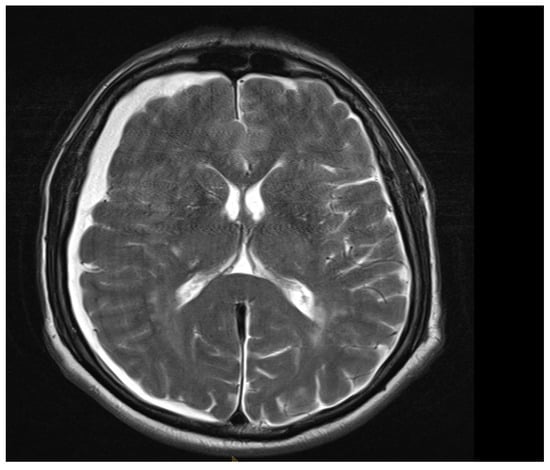

Among the 722 punctures, complications occurred in four cases (0.6%), see Table 3. Three of these complications arose after the first administration and one after the second. Reported complications included one case of post-puncture aggravation of pain, and one case of post-puncture headache. Both cases were managed conservatively using analgesics. In one case, shortness of breath occurred. In this patient, a cardiopulmonary event was ruled out, which required performing blood sampling as well as a CT-angiography of the pulmonary arteries. In another case, an intracranial subdural hygroma occurred, see Figure 2. No neurological deficits occurred, but due to persistent headache, an MRI scan was performed which revealed the diagnosis. The patient was readmitted for inpatient treatment for another 5 days 1 month after initial puncture. An MRI scan of the lumbar scan revealed epidural accumulations of cerebrospinal fluid at the thoracolumbar junction (Figure 3). Bed rest was ordered for 3 days. 2 days after readmission, a CT-guided lumbar blood patch was performed at the level L2 with 35 mL of blood, and oral analgesics were administered. The patient was discharged after five days. At subsequent follow-up visits, the patient reported no further headaches, and an MRI performed six weeks later demonstrated the complete resolution of the epidural cerebrospinal fluid collections (Figure 4).

Figure 2. Axial T2 MRI, showing subdural hygroma on the right side. The image was acquired 1 month after intrathecal injection due to persistent headache.